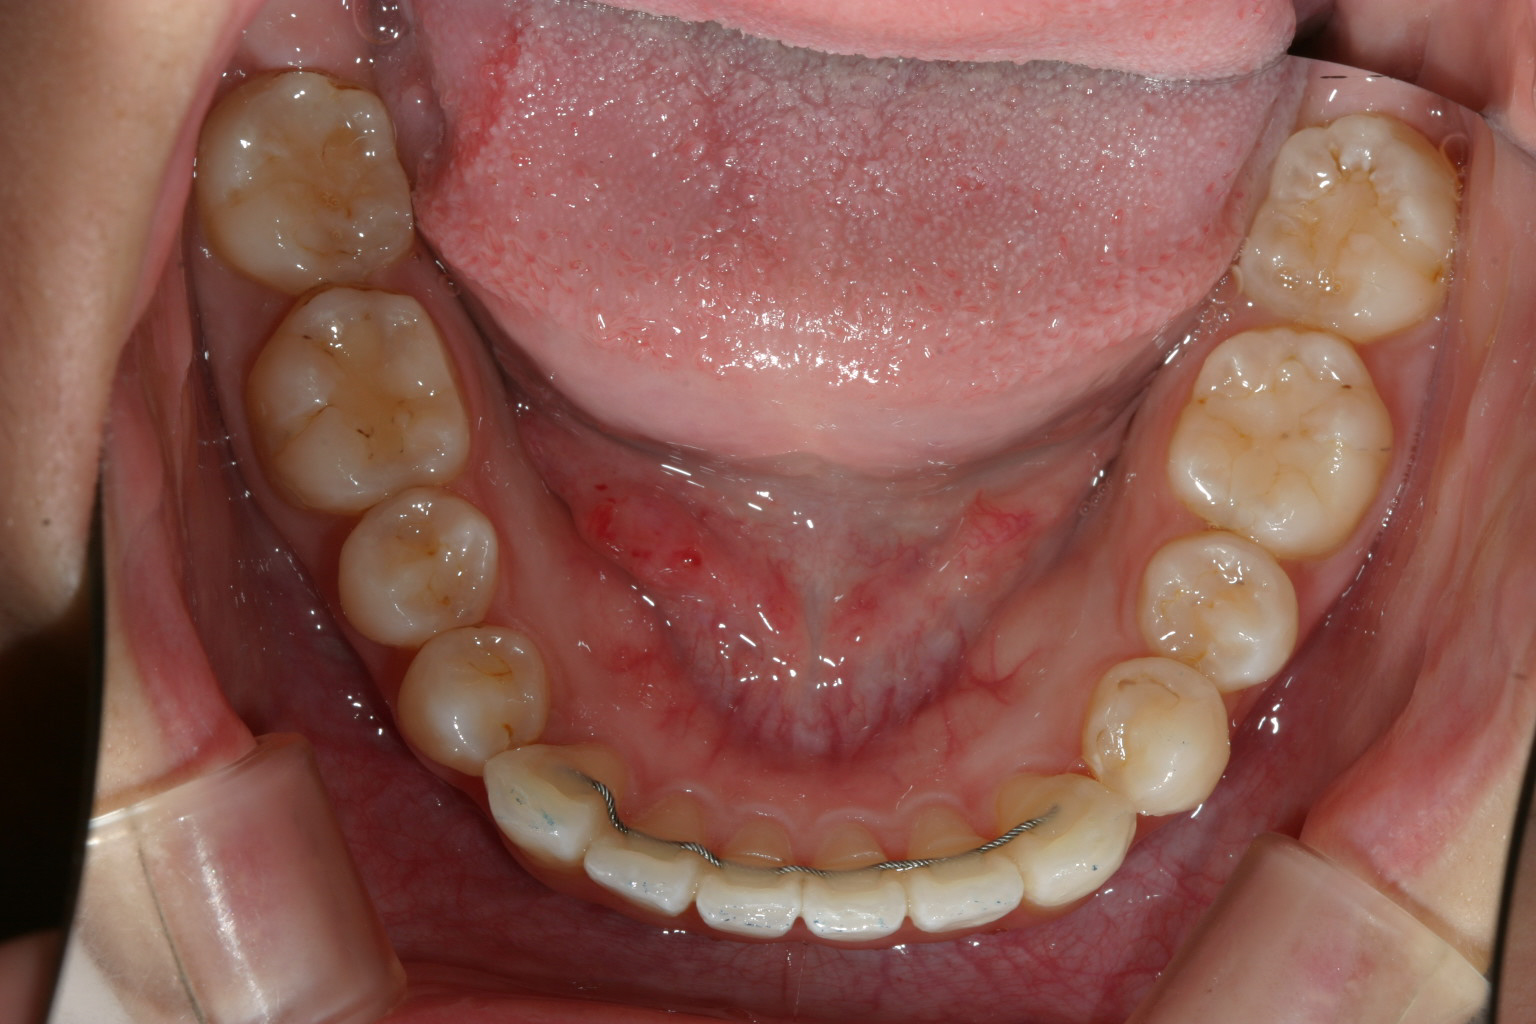

一生懸命インビザライン頑張って頂いたお陰で綺麗に改善致しました。

下顎は元々綺麗ですからあまり変化は無いです。

凄く綺麗に改善しました。 これは100点満点です。

大変綺麗に改善しました翼状捻転症例です。